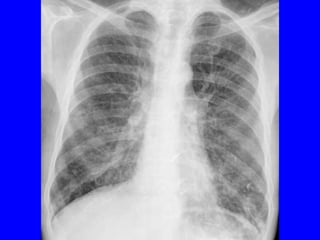

RADIOLOGICAL FEATURES

BRONCHIECTASIS

THE CHEST RADIOGRAPH

• Often normal if not severe

• Too many white lines extending from the hila

= tram-tracks

• Elongated (tubular) opacities (white)

• Small circles containing air (black) or fluid and

air (air-fluid level)

MILD BRONCHIECTASIS

Normal chest radiograph

presents with hemoptysis